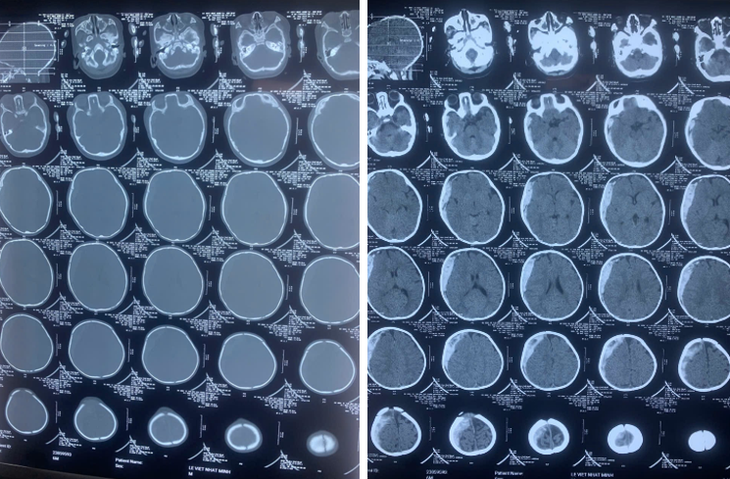

Theo đó, bệnh nhi nam 6 tháng tuổi vào cấp cứu trong khoa Ngoại Chấn thương, nhập viện trong tình trạng hôn mê, thở máy. Trẻ được chụp CT Scanner cắt lớp sọ não và có hình ảnh tụ máu dưới màng cứng lượng lớn, có chèn ép não vùng bán cầu não phải.

| Kết quả chụp CT Scanner cắt lớp sọ não thấy có hình ảnh tụ máu dưới màng cứng lượng lớn, có chèn ép não vùng bán cầu não phải - Ảnh BVCC |